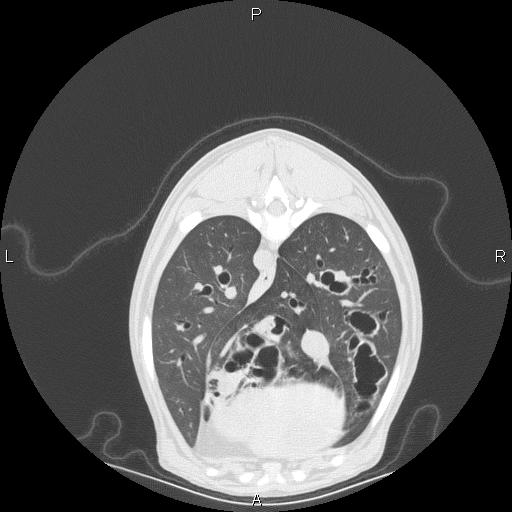

The main building features three surgical suites, one of which is exclusive to orthopedics; a special procedures room equipped with flexible and rigid endoscopy; a dedicated chemotherapy room with a biological safety hood for chemotherapy preparation; an in-house laboratory; and diagnostic imaging facilities with two digital radiology suites, an ultrasound and CT scanner. Magnetic resonance imaging (MRI) is available on-site. In 2014 we expanded our services to include animal rehabilitation, including a physiotherapy room (equipped with a water treadmill).